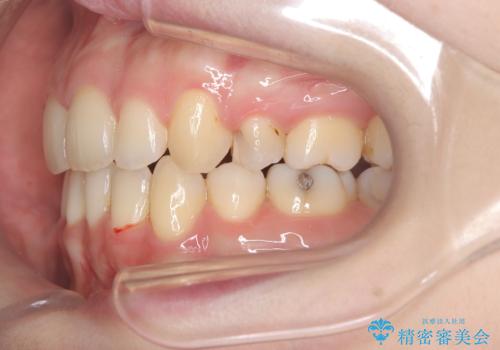

- 「歯のデコボコと前歯が出ているせいで口が閉じにくい」を主訴に来院された患者様です。

上下左右の4番(第一小臼歯)を抜歯をし審美ワイヤー装置で治療を行いました。

抜歯矯正により歯列のデコボコ(叢生)が改善し、前歯の突出も解消されたことで口元が下がり、すっきりとした印象となりました。